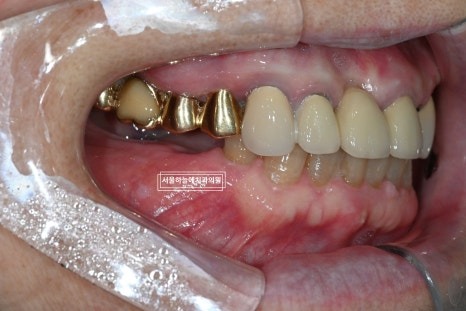

수술 후 약 1개월 반 정도 지난 뒤

아래 앞니 크라운 치료를 먼저 진행해 교합을 안정시킨 후

임플란트 2차 수술을 진행했습니다.

최종적으로 위아래 앞니

아래 양쪽 어금니 임플란트 보철까지

모두 안정적으로 마무리되었습니다.